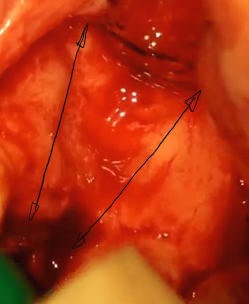

06/05/2011 à 09h19

le premier coté est en flap, avec incision palatine, en biseau, et le deuxième coté (droit) est en flapless, avec décollement de la partie vestibulaire, de la partie crestale et d'une petite partie palatine (2-3 mm), créant une espèce de chaussette, très lâche, que je distant pour introduire le greffon, d'où l'impression de flap, mais une fois remis en place, seulement trois points de suture.